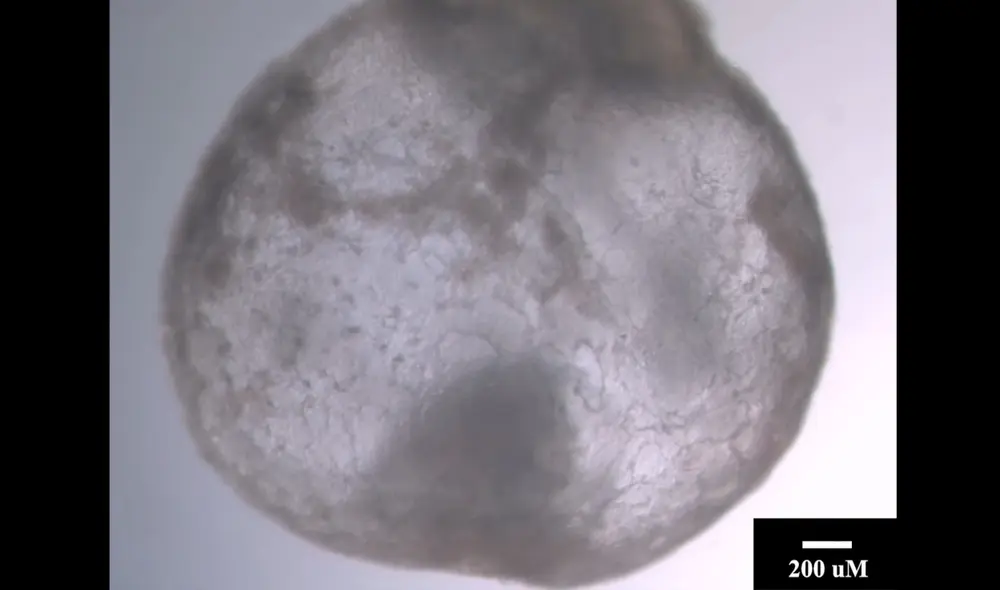

En el siguiente vídeo se puede ver el embrión en su día 9 de desarrollo, con un corazón que late, un saco vitelino, una placenta y una circulación sanguínea emergente

Embrión sintético de ratón desde el primero hasta el octavo día de crecimiento. Foto: Weizmann Institute/Times of Israel